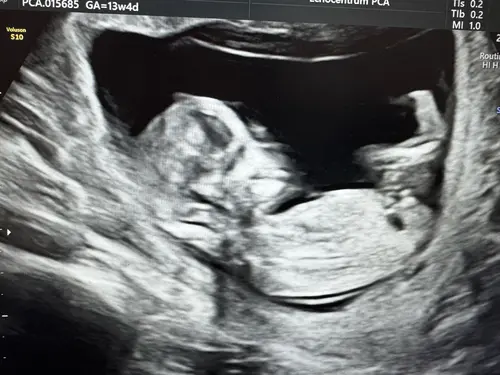

Nu ben ik toch ook wel heel nieuwsgierig. Heeft iemand een idee? 🩷💙

Beste NUB tuurders. Wij zijn enorm nieuwsgierig. Wie durft een gok te wagen?